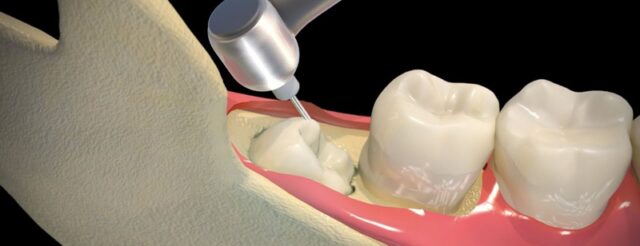

• Áp dụng công nghệ hiện đại: Việc sử dụng các công nghệ như máy Piezotome (máy nhổ răng siêu âm) giúp việc nhổ răng trở nên nhẹ nhàng, ít đau, ít sang chấn và thời gian hồi phục nhanh hơn.

• Phẫu thuật: Với răng ngầm sâu, bác sĩ thực hiện tiểu phẫu nhẹ nhàng để lấy răng.